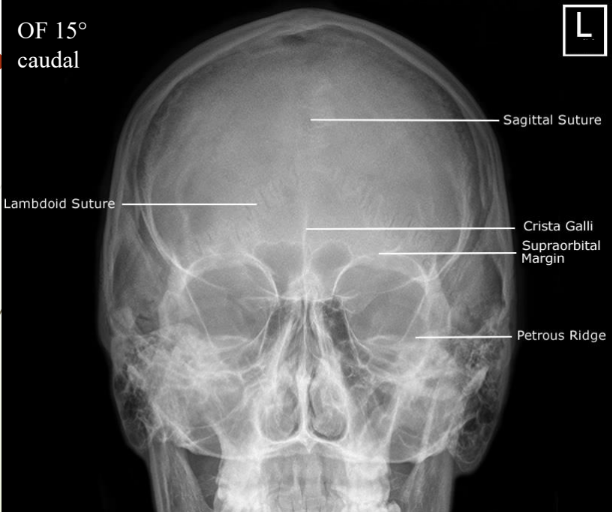

How is 15 degree caudal angulation for OF projection perfomed?

knowt flashcard image